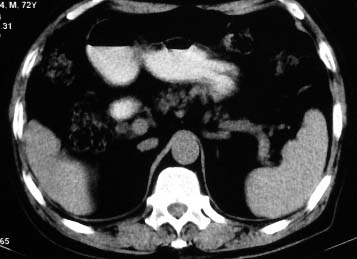

男 56 腹部不舒

典型肝硬化:1、肝各叶大小的比例失常;2、肝表面明显凹凸不整,边缘变钝;3、肝实质密度一般与正常肝无明显改变;4、肝裂增宽;5、门静脉增宽,脾静脉扩张扭曲;6、脾脏虽然不大,但不是所以肝硬化的脾脏都增大。

典型肝硬化:1、肝各叶大小的比例失常;2、肝表面明显凹凸不整,边缘变钝;3、肝实质密度一般与正常肝无明显改变,但肝右叶似可见再生结节影;4、肝裂增宽;5、门静脉增宽,脾静脉扩张扭曲;6、脾脏增大. 脾脏大小的标准有:1脾脏的左右径(大于5个肋单元) 2脾脏的宽度 3脾脏的上下径(超过肝下缘) 请参考.

影像表现上基本符合肝硬化,但肝缘还算光整,脾也不大<脾下缘低于肝下缘不能作为判断脾大的标准吧>胃底静脉曲张也不明显,还是先结合病史吧,会不会先天就这样呢.

本例病例的诊断,肝脏的表现出现了一些肝硬化的征像,但我觉不能武断的诊断为肝硬化;我会如下诊断:肝脏改变,请结合临床,生化检查,排除肝硬化.

就本病例而言,楼上的战友可能有点优柔寡断。如果是先天性肝脏形态异常,那么它的密度异常就不符合了吧?仔细看,的确如多位战友所言,肝脏密度不均匀,有再生结节,考虑肝硬化应该不会出错。当然,楼上战友那样写报告是最保险的,我也会这么写,我们在实际工作中都应该学会自我保护。

肝硬化表现符合,肝脾ct值有倒置,考虑局灶性肝脂肪浸润